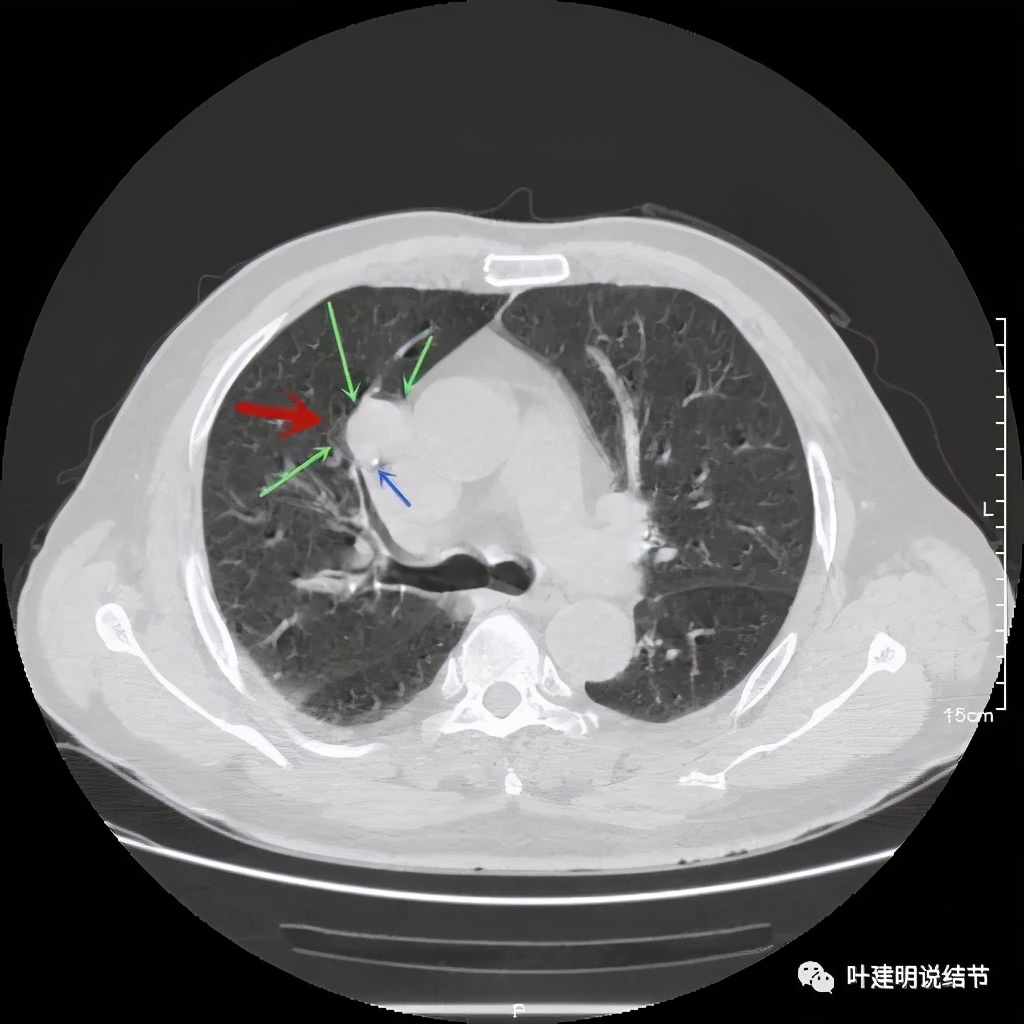

上图示病灶局部点状高密度(蓝色);边缘过于光滑(绿色)

上图示病灶密度不均,但边缘过于光滑(绿色);支气管似有截断(粉色);局部有点状钙化(蓝色)